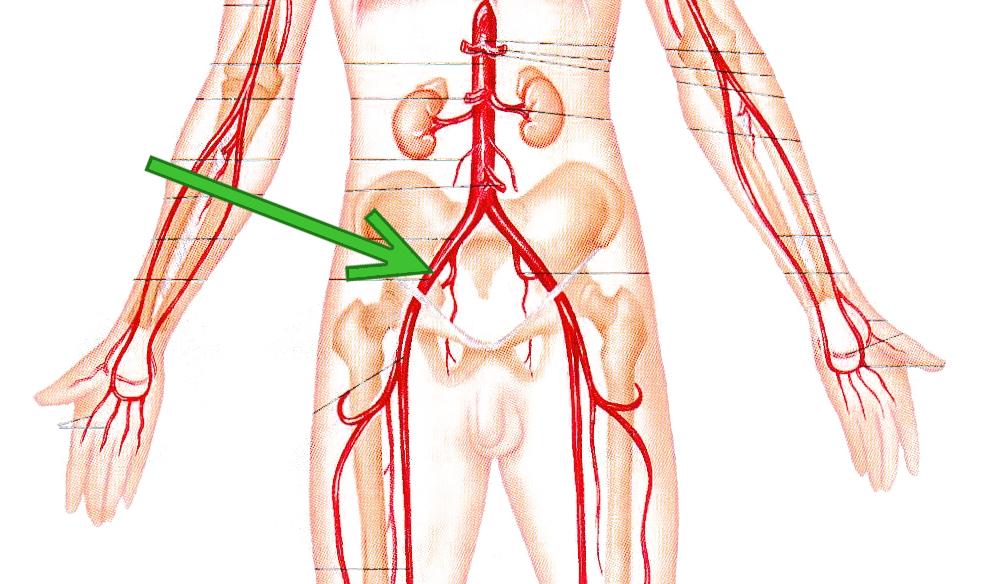

Особенности и диагностика левостороннего кровотока